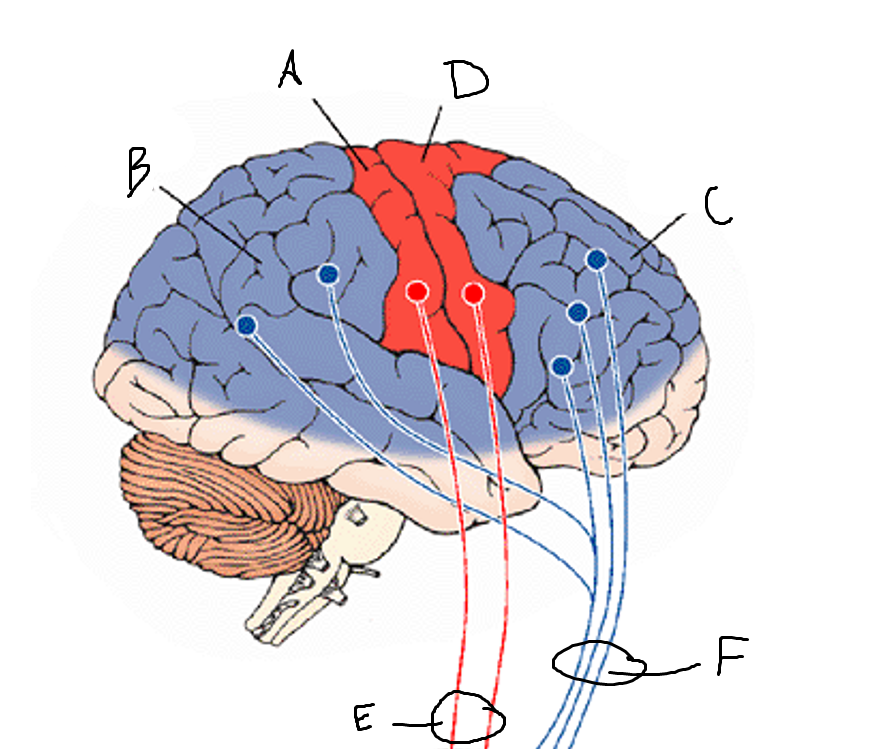

basal ganglia

A

somatosensory cortex

B

parietal association cortex

C

frontal and prefrontal cortices

D

primary motor cortex

E (where are the projections?)

putamen

F (where are the projections?)

caudate